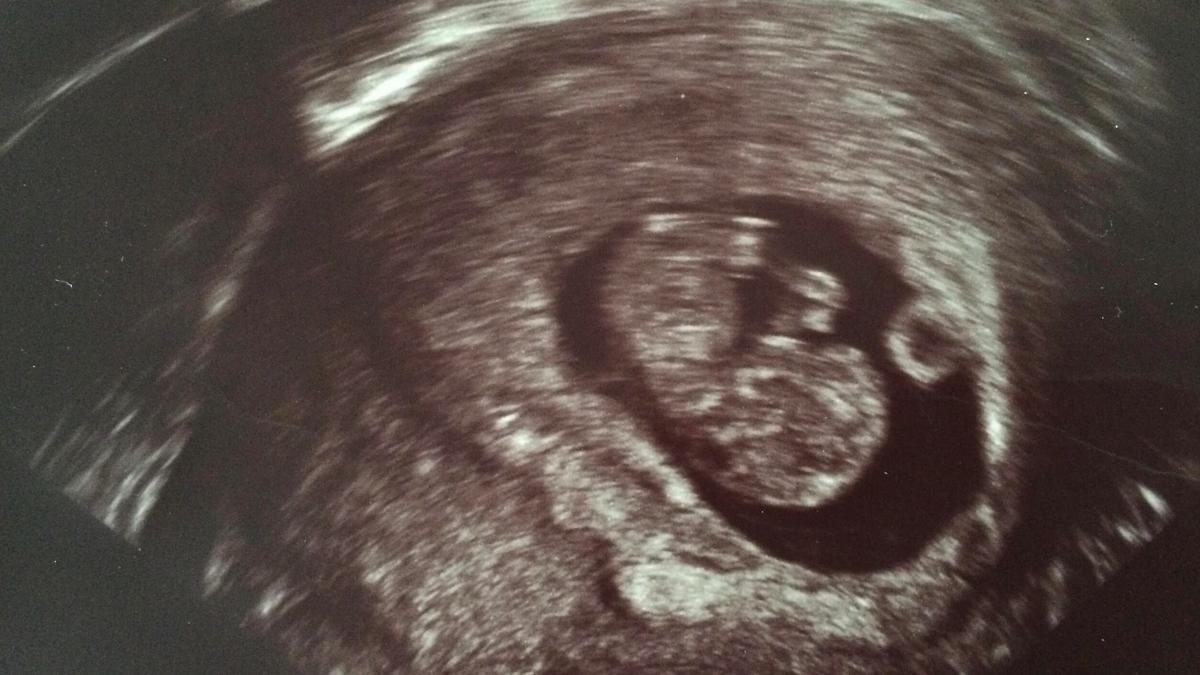

We gingen er weer met frisse moed tegenaan. Poging 4 alweer. Van te voren was ik, zoals zo vaak tijdens dit traject, weer aan het Googelen geslagen. Ik was erachter gekomen dat veel dames Utrogestan langer door slikten, soms wel tot 16 weken (mits ze zwanger waren uiteraard). Ik stelde dit voor aan de gynaecoloog en hij vond ook dit weer prima. Ik kreeg dit keer voor 12 weken Utrogestan mee na de IUI. En toen, na al die vele en vele pogingen, hebben we op dag 15 voor het eerst een test gedaan. Daarvoor was het nooit nodig, want ik haalde dag 15 immers nooit. Met trillende handjes deed ik de test en legde hem weg voor een paar minuutjes. Zo spannend. Mijn hart zat in mijn keel. En toen we keken, na die eindeloze minuten, stonden daar twee streepjes! Het was ein-de-lijk gelukt! Ik was zwanger!